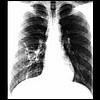

二、X線檢查對於肺部損害如麴黴球、肺麴黴病等有幫助。